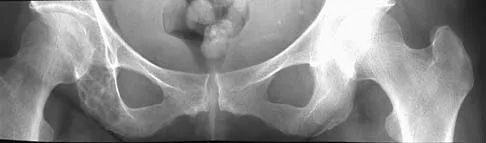

A 61-year-old man reports right hip pain and limited motion after undergoing total hip arthroplasty for posttraumatic arthritis 1 year ago. Figure 6 shows an AP radiograph of the pelvis. To improve motion and relieve pain, management should consist of

Explanation

The patient has symptomatic grade IV Brooker heterotopic ossification. Once the bone has matured, it can be excised. Surgical excision should be combined with postoperative irradiation to avoid recurrence. Pharmacologic and irradiation intervention are not successful beyond the perioperative period unless they are combined with surgical excision of mature heterotopic ossification. Koval KJ (ed): Orthopaedic Knowledge Update 7. Rosemont, IL, American Academy of Orthopaedic Surgeons, 2002, pp 417-451.